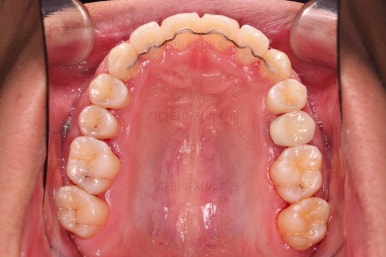

초진 시 입안의 모습입니다.

부정교합이 있고요.

윗니와 아랫니가 앞뒤로 지그재그 서로서로 껴있어야 좋은 교합인데 전반적으로 윗니가 앞으로 밀려있는 양상의 교합이에요.

또한 눈에 띄는 모습은 앞니가 튀어나오고, 사이사이 틈새가 보인다는 점이에요.

치열이 매우 가지런해졌고 틈새도 없어졌으며 교합도 잘 맞아졌어요.

사이가 다시 벌어지거나 틀어지지 말라고 치아 안쪽면으로 부착형 철사 유지장치를 붙이고 마무리를 했어요.